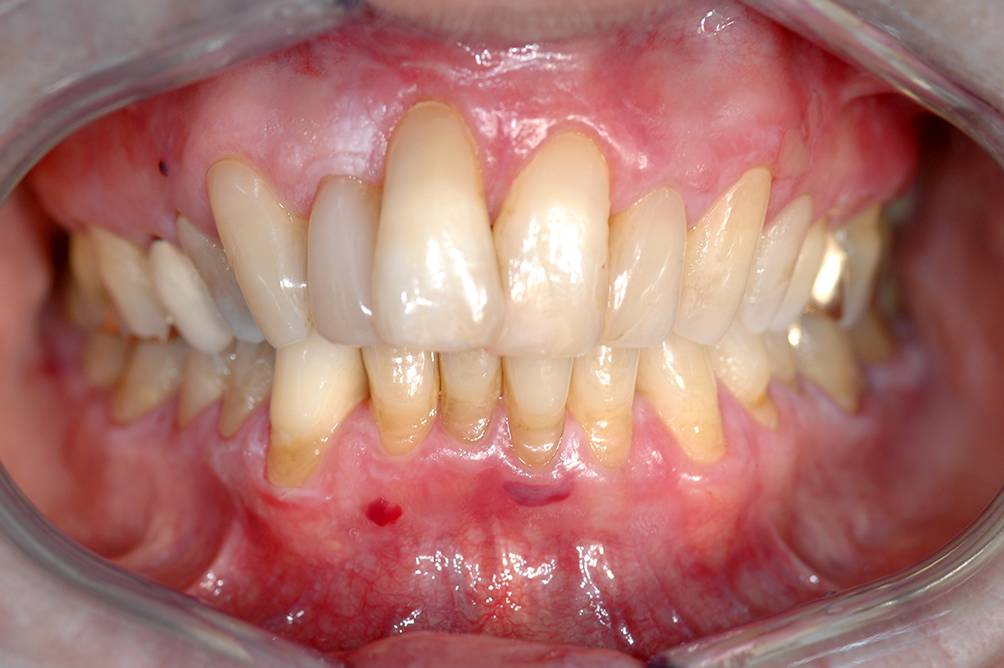

Abb. 6

Atrophische Form eines oralen Lichen planus (OLP) an der bukkalen keratinisierten Gingiva v. a. im Oberkiefer bei einer 75-jährigen Patientin. Neben den roten Zonen sind auch sehr dezente weiße, teils retikuläre Effloreszenzen erkennbar. Mitunter klagen die betroffenen Patienten bei diesem OLP-Typ über ein Brennen an den betroffenen Mukosaregionen

Bild vergrößern